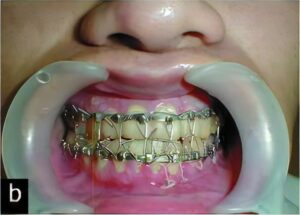

顎変形症 (受け口などの上下の顎のバランスが悪い方や顎の変形で正しく噛み合わない) の方に関しても矯正治療と手術(顎矯正手術)が必要になる場合があります。群馬大学や新潟大学医歯学総合病院顎顔面外科口腔外科診療室にご紹介しております。

唇顎口蓋裂等の方、顎変形症の方における歯科治療(う蝕治療・歯周治療・抜歯など)は当院で行っています。